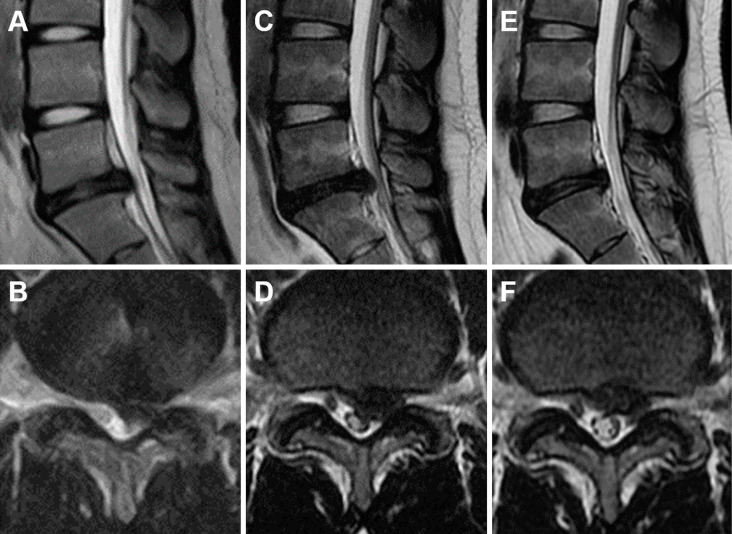

Results: Groups Y and A consisted of 15 and 123 patients, respectively. Condoliase therapy was effective in 9 patients (60.0%) in Group Y and 96 patients (78.0%) in Group A. The rates of Pfirrmann grade deterioration and recovery were substantially higher in Group Y than in Group A (83.3% vs. 45.8% and 50.0% vs. 16.3%, respectively). While the disk height reduction in Group Y was greater at 3 months, it recovered to the same level as that in Group A at 1 year. In Group Y, patients who did not respond to the treatment exhibited a considerably higher preoperative ODI (P<0.05).